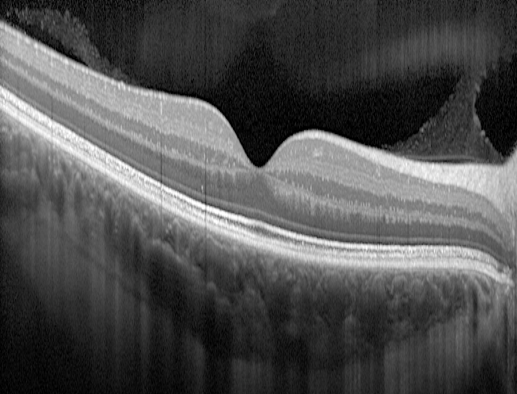

OCT : Tomographie à Cohérence Optique

OCT Maculaire : La tomographie à cohérence optique est une technique d'imagerie non contact, non invasive et indolore permettant d'obtenir des images en coupes de la rétine dans toute son épaisseur. Son importante résolution permet d'obtenir une segmentation des différentes couches de la rétine et de quantifier l'épaisseur rétinienne.

OCT — Rétine normale

OCT — DMLA humide (néovaisseaux)